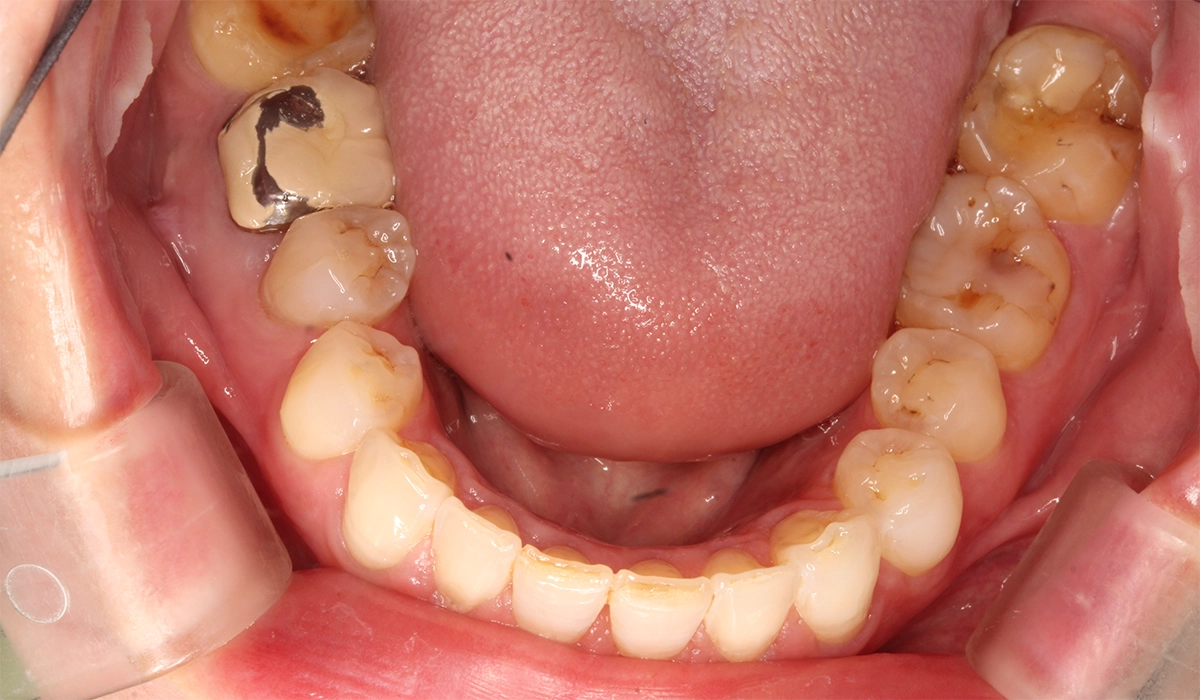

術前:下顎